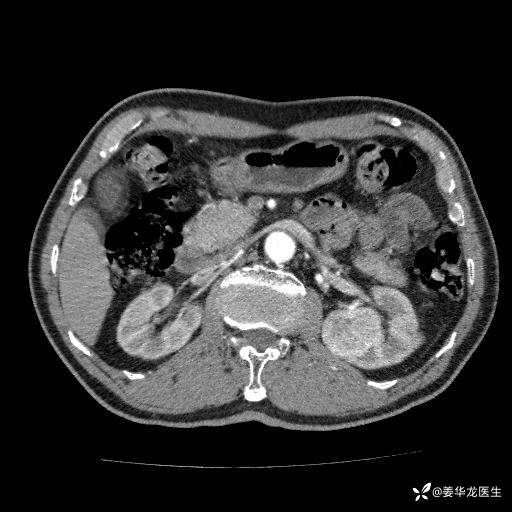

左肾中心型肾门部肿瘤39mm×34mm×36mm,右肾GFR25ml/min,部分切还是全切?

患者75岁老年男性,体重50kg,无高血压、肾病、糖尿病等基础病,检查发现左肾中心型肾门部肿瘤,右肾GFR只有25ml,无肉眼血尿,无镜下血尿。入院验血常规检查均正常,包括肾功能,肌酐102.7umol/L.

二、左肾肿瘤与左肾集合系、左肾动静脉关系密切,左肾部分切除术可行吗?成功率有多大?成功部分切后,肾功能还有多少?

四、左肾根治疗切除术后,透析的机率有多大?